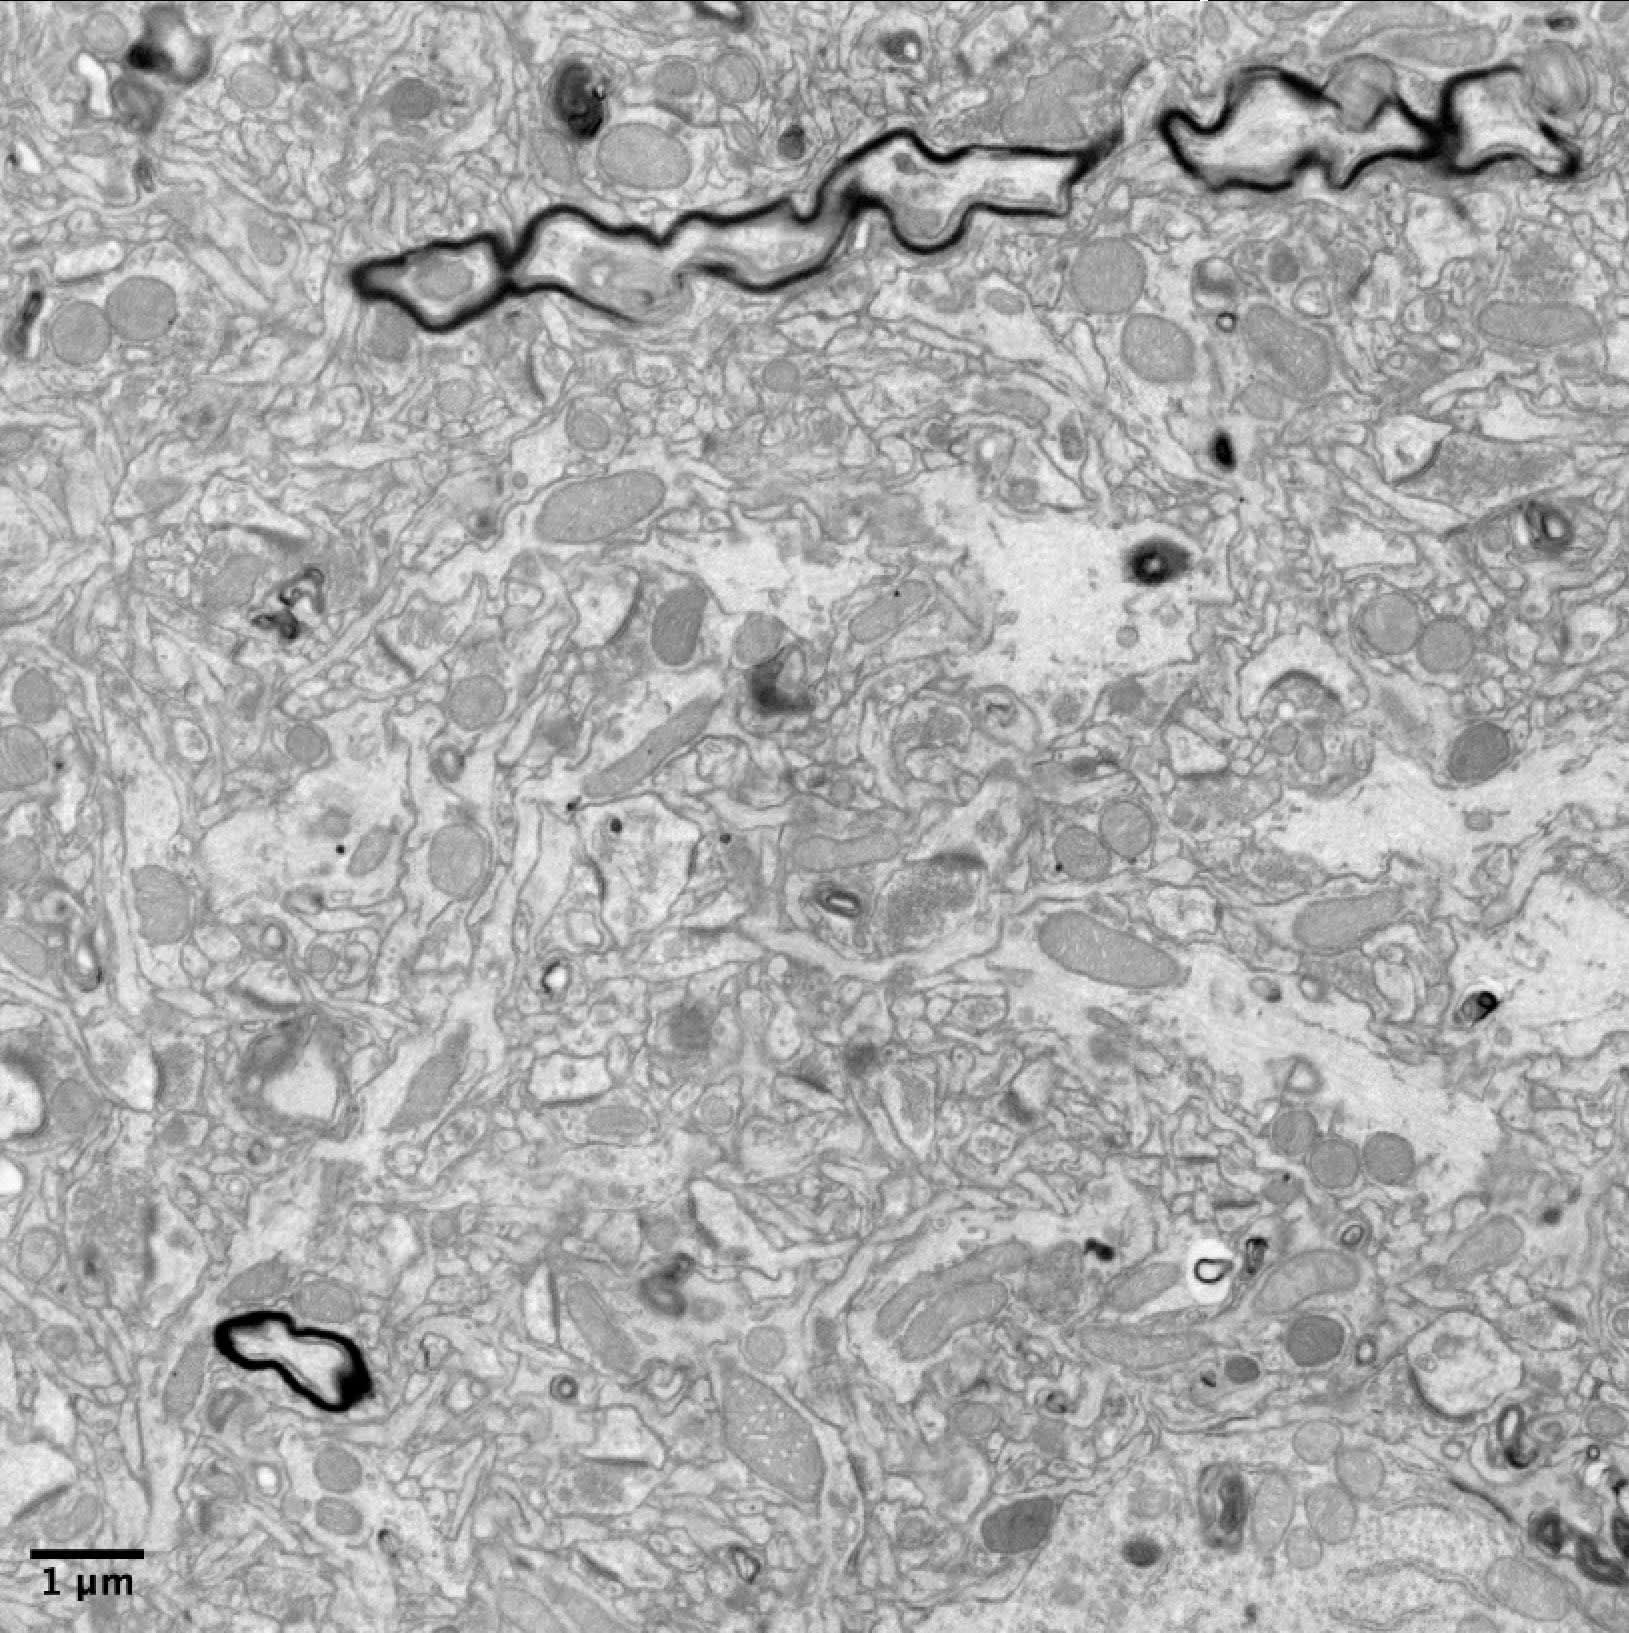

Sample from a rat brain preserved using Nectome’s methods, then stored at 60°C for 12 hours (“hot” storage). Electron microscopy performed at the Berkeley EM Core. Click here to see the complete dataset.

Sample from a rat brain preserved using Nectome’s methods, then stored at −32°C for 12 hours (“cold” storage). Electron microscopy performed at the Berkeley EM Core. Click here to see the complete dataset.

After examining the electron micrographs and consulting with several neuroscientists, Andrew determined that our preservation was excellent, that the brain was connectomically traceable, and that both the “cold” and the “hot” slices were of near-identical preservation quality. He recommended us for a $550,000 investment, which we’ve since received.

A single synapse from our rat brain demo, preserved after 5 minutes of ischemia and stored at 60°C for 12 hours. The dark curve is the junction between the two neurons. Those tiny grains at the bottom of the synapse are individual vesicles, still filled with neurotransmitter, suspended in place by fixation. The larger gray sphere near the vesicles is a mitochondria that helps power the synapse. You can see individual cytoskeletal details. The individual proteins are also still there, though they’re not distinguishable at this level of resolution. This is what I mean by “subsynaptic” preservation.